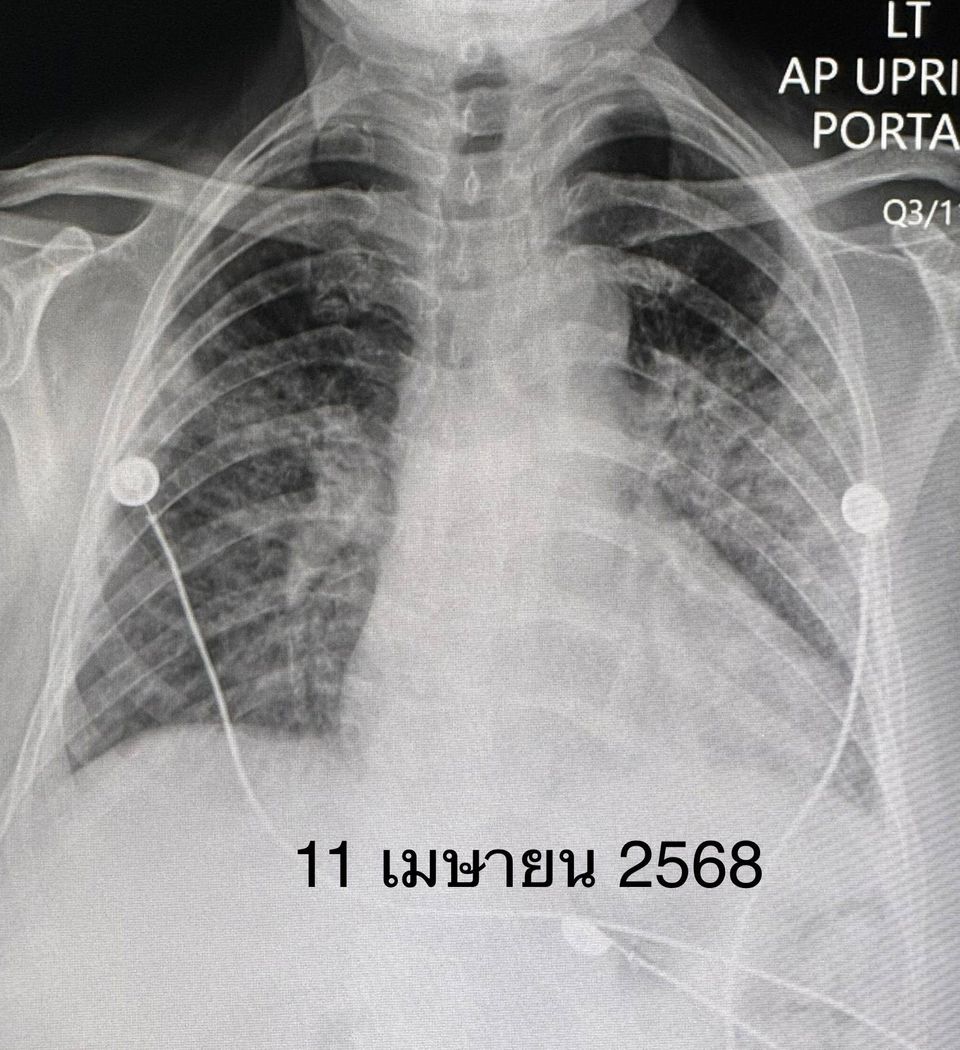

เจาะเลือด พบเลือดจางเล็กน้อย ค่าอักเสบในเลือด ESR และ hs-CRP สูง, ANA ปกติ ค่าโซเดียมในเลือดต่ำ เอกซเรย์ปอดและคอมพิวเตอร์ปอดพบปอดอักเสบทั้ง 2 ข้าง แยงจมูก ส่งเลือดเพาะเชื้อ ส่องกล้องเข้าไปในหลอดลม ไม่พบการติดเชื้อแบคทีเรีย ไวรัส เชื้อรา หรือวัณโรค ได้ยาปฏิชีวนะ เอกซเรย์ปอดซ้ำไม่ดีขึ้น หลังรักษาที่โรงพยาบาลใกล้บ้าน 26 วัน ญาติขอย้ายมารักษาต่อวันที่ 11 เม.ย.68

วินิจฉัยว่า ผู้ป่วยรายนี้เป็นโรคภูมิต้านทานตัวเองชนิด Anti-MDA5 antibody positive dermatomyositis ทำให้เนื้อเยื่อปอดอักเสบ และปอดเกิดพังผืดอย่างรวดเร็ว ไม่มีกล้ามเนื้ออ่อนแรง ไม่มีความผิดปกติของผิวหนังให้ยาสเตียรอยด์ชนิดฉีดขนาดสูง ต่อมาเปลี่ยนเป็นชนิดกิน ยากดภูมิคุ้มกันไมโคฟีโนเลต (mycophenolate) ยาไฮดรอกซีคลอโรควิน (hydroxychloroquine) และยา Tolvaptan รักษาโรคโซเดียมในเลือดต่ำ

หลังได้รับยา คนไข้เหนื่อยน้อยลง ระดับออกซิเจนที่ปลายนิ้วดีขึ้น ใช้ออกซิเจนแบบหนวดกุ้งธรรมดาทางจมูก ไม่ต้องใช้ High-Flow nasal O2 cannula เอกซเรย์ปอดดีขึ้นช้า ๆ ลุกขึ้นเดินได้ ระดับโซเดียมในเลือดเกือบปกติ กลับบ้านได้หลังจากรักษาอยู่ในโรงพยาบาล 15 วัน หมอนัดติดตามเป็นคนไข้นอกต่อไป